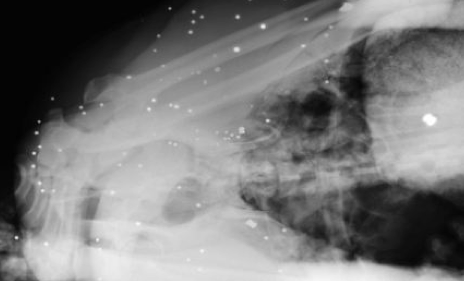

Nyt verkossa on julkaistu röngtenkuvia kuolleesta Fred-nimisestä paviaanista, joka aiheutti kauhua Etelä-Afrikan Kapkaupungin asukkaiden keskuudessa. Vandaalin maineen saanut paviaani ammuttiin kuoliaaksi sen väkivaltaisen ja uhkaavan käytöksen takia. Eläinlääkärien julkaisemat röngtenkuvat paljastavat, että Fred-paviaaniin on ammuttu yli 50 luotia. Kuvissa nähdään, kuinka paviaanin vartalossa näkyy valkoisia luodinjälkiä.